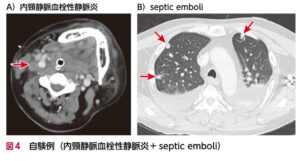

⑤Lemierre症候群(レミエール症候群)

| 疫学 | 稀な疾患、若年成人に多いとされている |

| 病態 | 口腔・咽頭領域の先行感染(齲歯、急性扁桃炎、扁桃膿瘍など)の後に、炎症が内頸静脈に波及し、血栓性静脈炎を生じ、血行性に全身に行き(菌血症)、全身の膿瘍形成を伴う疾患(敗血症性肺塞栓症など)。 |

| 原因菌 | 起炎菌の70%は嫌気性菌のFusobacteriun necrophorun |

| 症状 | ①先行する歯痛・咽頭痛→頸部の激痛と腫脹 |

| 検査 | 血液検査:炎症反応高値 頸部造影CT:内頸静脈内に血栓が造影不良域として描出 胸部CT:敗血症性肺塞栓症(両側びまん性すりガラス影、胸膜に接する楔形陰影など) ![]() |